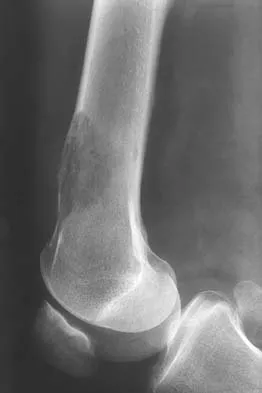

Question 14 High Yield

A 51-year-old woman has had progressively increasing right knee pain for the past 6 months. She has a history of metastatic renal cell carcinoma to the lung and the skeletal system. Radiographs are seen in Figures 18a and 18b. The next step in management of the right distal femur lesion should consist of

Detailed Explanation

In a patient with known metastatic disease, the surgeon must rule out additional lesions throughout the femur prior to surgical management. Lesions located in the diaphysis or in the peritrochanteric region may influence the surgical procedure. Frassica FJ, Gitelis S, Sim FH: Metastatic bone disease: General principles, pathophysiology, evaluation, and biopsy. Instr Course Lect 1992;41:293-300.